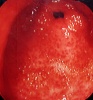

שיטת האבחנה העיקרית היא הגסטרוסקופיה המאפשרת לראות היטב את הכיב ומיקומו, ואת השינויים ברקמה שסביב לכיב. הדיוק האבחנתי של הגסטרוסקופיה הוא 95%. הגסטרוסקופיה מאפשרת לאבחן את מקור הדימומים הפעילים (תצלומים 3.3) וכן ליטול ביופסיות מממצאים חשודים ולקבל אבחנה היסטולוגית. הגסטרוסקופיה חשובה לאבחנה מבדלת בין דימום שמקורו בדליות הוושט (תמונה 4.3) לבין דימום שמקורו בקיבה או בתריסריון. כיב חוזר בקו ההשקה, קרעים ברירית (בתסמונת על-שם מלורי-וייס (Mallory-Weiss)) (תמונה 5.3), דלקת קיבה וארוזיות ניתנים לאבחנה ולהוכחה, בעיקר בעזרת הגסטרוסקופיה, ואין אפשרות להדגימם כראוי ברנטגן (תמונה 2.3 , 6.3).